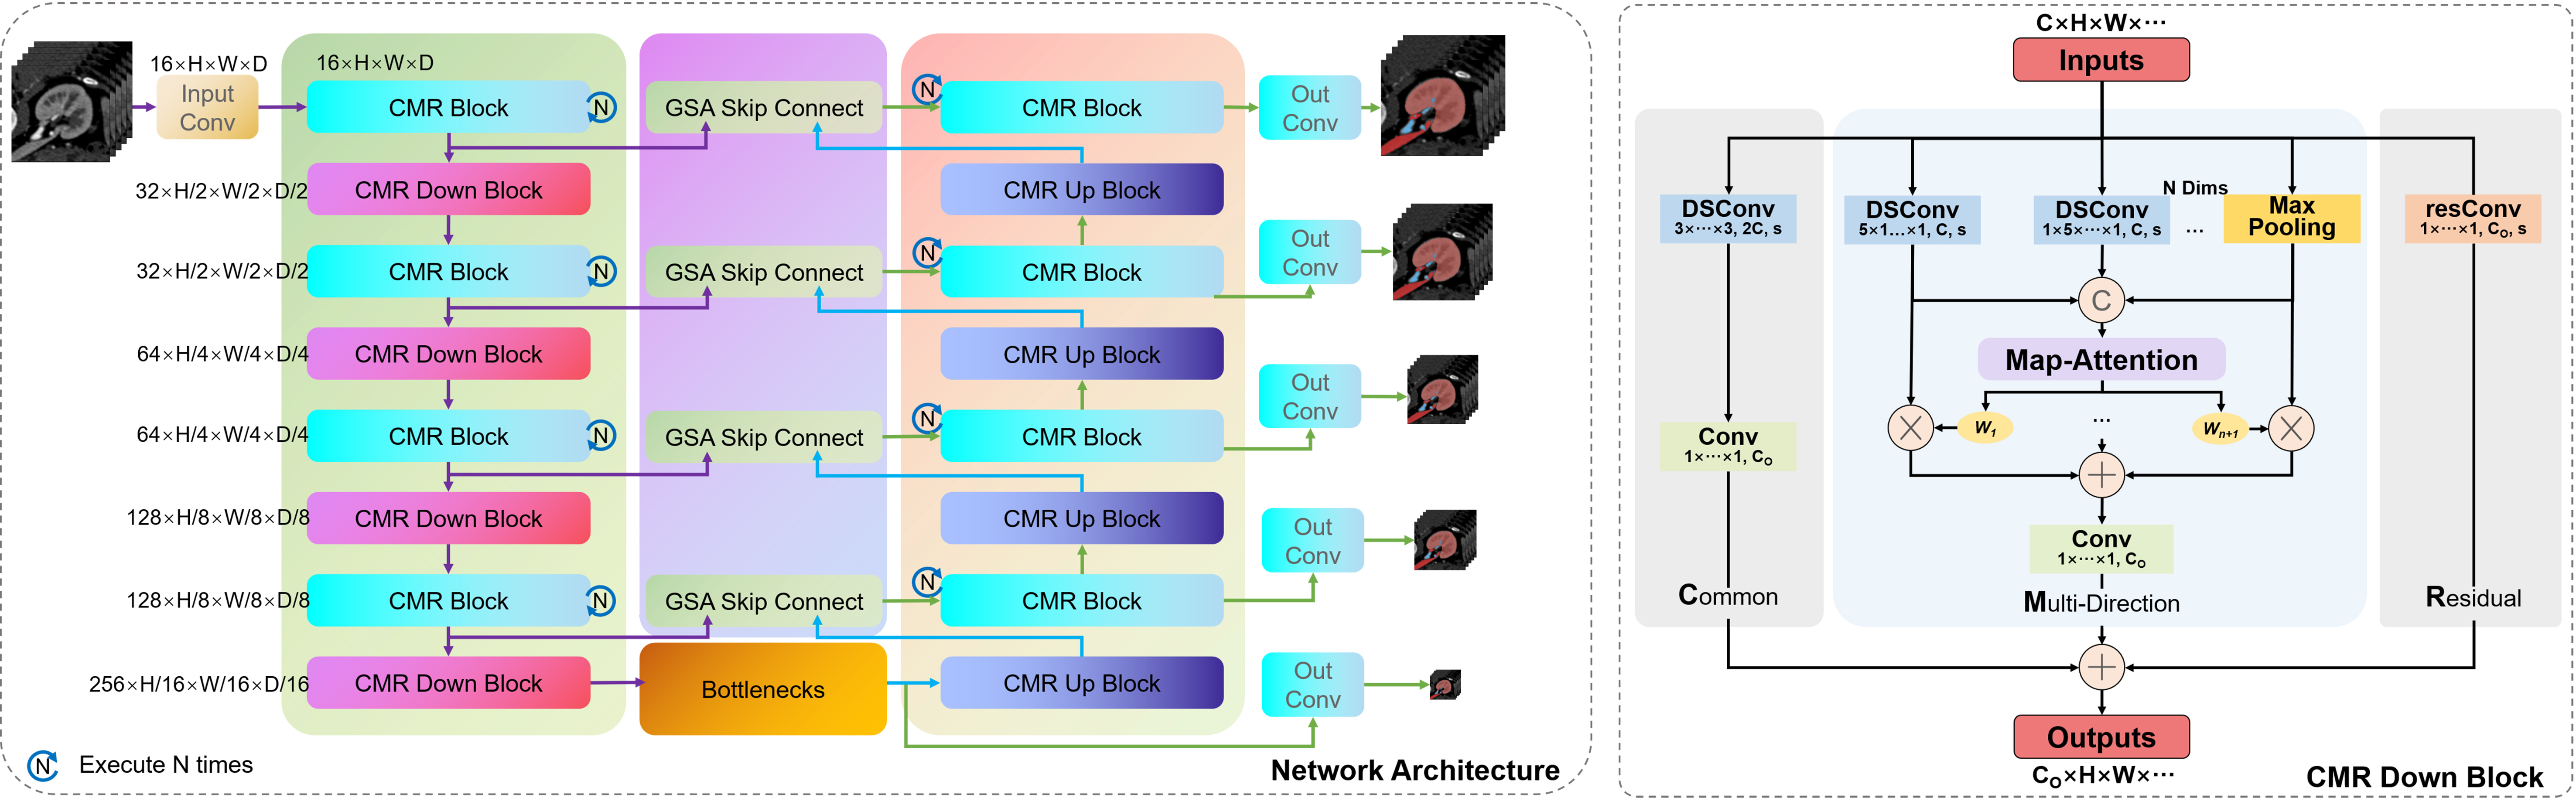

Unlike deformable convolution, which requires learning an offset, we directly design strip-shaped convolution modules in different directions to adapt to offsets representing the direction of slender structures. The attention mechanism we designed and the encoder-decoder module common and multi-direction with residual (CMR) Block integrated on it are shown in Figure 3.

Figure 3. Multi-directional attention module and CMR Block based on it. CMR: Common and multi-direction with residual.

Due to the uncertain shape of slender structures, block convolution without directional features is often difficult to extract effective coherent information of slender structures. In contrast, strip convolution with different axes is more conducive to adapting to slender structures. Therefore, in the early stage of the multi-directional attention unit, we first use a 5-pix strip convolution for feature extraction for different axes of the image. The convolution results obtained in different directions are as follows.

Through this processing mechanism that integrates multi-directional strip convolution results, the multi-directional attention module can combine attention weights to overcome the impact of convolution kernel weight sharing on feature extraction, and better help pixels find the adjacent pixels with the highest correlation in their neighborhood, thus achieving adaptation to slender structures. As shown in the upper right corner of Figure 3, for a circular arc curve that can represent any direction of slender structures, the feature map processed by the multi-directional attention module better preserves the original features of the curve compared to the feature maps of traditional convolution, without being mixed by background pixels. Besides, in order to minimize computational complexity, we introduced the depthwise separable convolution[20] into the module instead of using traditional convolution method.

In addition, the CMR block is composed of three parts: regular convolution block, multi-directional attention block and residual convolution block. The function of common convolution blocks is to preserve the feature extraction capability of traditional convolution; The function of multi-directional attention blocks is to focus on the distribution of slender structures; The function of residual convolution blocks is to ensure better semantic coherence and alleviate the gradient vanishing/exploding problem caused by the network being too deep.

For segmentation task, we designed a network architecture as shown in Figure 4. It should be noted that the CMR Block is executed multiple times in a stage of the network. Because when the multi-directional attention module is executed only once, the receptive field range of the model is only on the coordinate axes of each dimension corresponding to the current pixel point, while multiple executions can expand the receptive field to the entire cube around it.

Figure 4. CMR U-Net: the network architecture based on CMR Block. CMR: Common and multi-direction with residual.

In addition, for the down-sampling and up-sampling units of the net, we use stride 2 convolution and transpose convolution, respectively, to replace the convolution settings of CMR Block. It is worth noting that we have also introduced max pooling operation in the multi-directional attention mechanism of the down-sampling unit, which can help avoid information loss of slender structures during the convolution down-sampling process with a stride of 2.

For the network, the skip connection mechanism and the bottleneck layer are also important units. Here, we have made improvements to these two units by proposing a skip connection fusion mechanism based on gated spatial attention (GSA) and a bottleneck layer based on axial attention. However, the only effective mechanism in practice is the skip connection fusion mechanism, which will be introduced in later experiments.

In the classic U-Net network model, the role of the skip connection layer is to fuse the low-level feature information of the encoder and the high-level semantic information of the decoder at the same resolution to ensure feature reusability, and to help the decoder stage recover the original pixel information of the up-sampled image, usually using channel concatenation for fusion. However, for 3D and even higher-dimensional images containing other information, the computational cost of channel concatenation cannot be ignored. Therefore, in medical images, the commonly used skip connection fusion strategy adopts the point-wise addition operation. It should be noted that although point-wise addition can reduce computation, this direct summation of high-level semantic information and low-level feature information without distinction may disrupt the coherence of the original semantic information, thereby reducing the reliability of the network. Therefore, here we propose a skip connection fusion strategy based on GSA, as shown in Figure 5.

This module combines the output image of the encoder part and the up-sampled image of the decoder part. Firstly, the two are concatenated in the channel dimension, and then the concatenated result is jointly fed into a regular convolution with a kernel size of 1. The output is a convolution result with 1 channel and a size equal to the input image size, which is activated by the Sigmoid function to become the spatial attention weight of the encoder image. This weight combines the information of low-level feature images and high-level semantic images, and is a learnable dynamically adjustable fusion weight. Finally, by weighting the encoder image and adding it point by point to the decoder image, the semantic coherence of the fused image is ensured.

In addition, we also introduced axial attention mechanism to the bottleneck layer of the network, which was proposed by Ho et al.[21] [Figure 6]. Axial attention is used to extract relevant information between different parts of the image, and is applied in low-resolution images to reduce computational complexity.